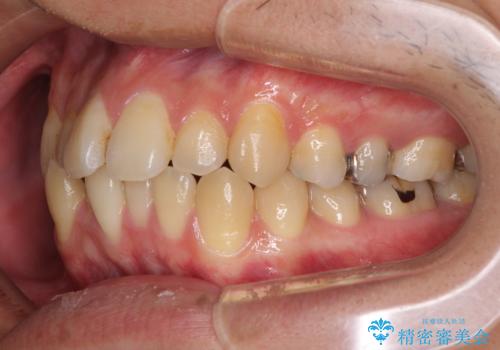

前歯のクロスバイトをインビザラインで矯正治療

- 前歯のデコボコとクロスバイトを気にして来院された患者様です。

前歯を早く整えたいとの希望があったので、ワイヤー矯正にて短期間でクロスバイトを解消し、その後インビザラインにて整えることとしました。

インビザラインによる前歯のクロスバイト改善におけるリスクとして、前歯歯髄充血・歯髄壊死が挙げられます。

ワイヤー矯正を併用する目的として、短期間でデコボコやクロスバイトを改善する他に、歯髄充血リスクを低減させるというものがあります。